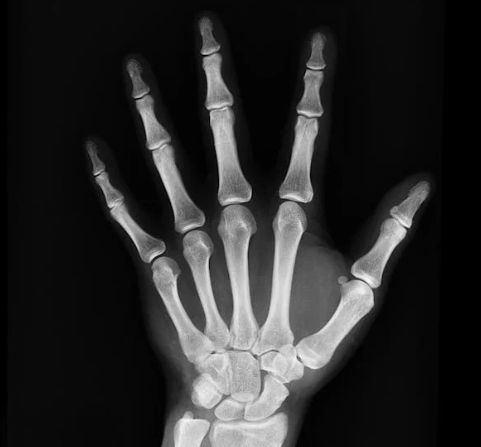

병원에서 건강검진이나 진료를 받다 보면 “엑스레이를 자주 찍어도 괜찮을까?” 하는 궁금증이 생기곤 합니다. 특히 치과, 정형외과, 내과 진료에서 엑스레이(X-ray) 촬영은 흔히 시행되는 검사 중 하나이죠. 하지만 방사선이라는 단어만 들어도 왠지 몸에 해롭지 않을까 걱정이 앞서기도 합니다.

왜냐하면 의료 목적의 방사선 검사는 위험보다 이득이 훨씬 크기 때문입니다. 예를 들어, 폐렴을 조기에 진단하거나 골절 부위를 확인하지 못하면 건강을 해칠 수 있는데, 엑스레이 검사는 이 문제를 빠르게 발견해 치료 기회를 제공합니다.